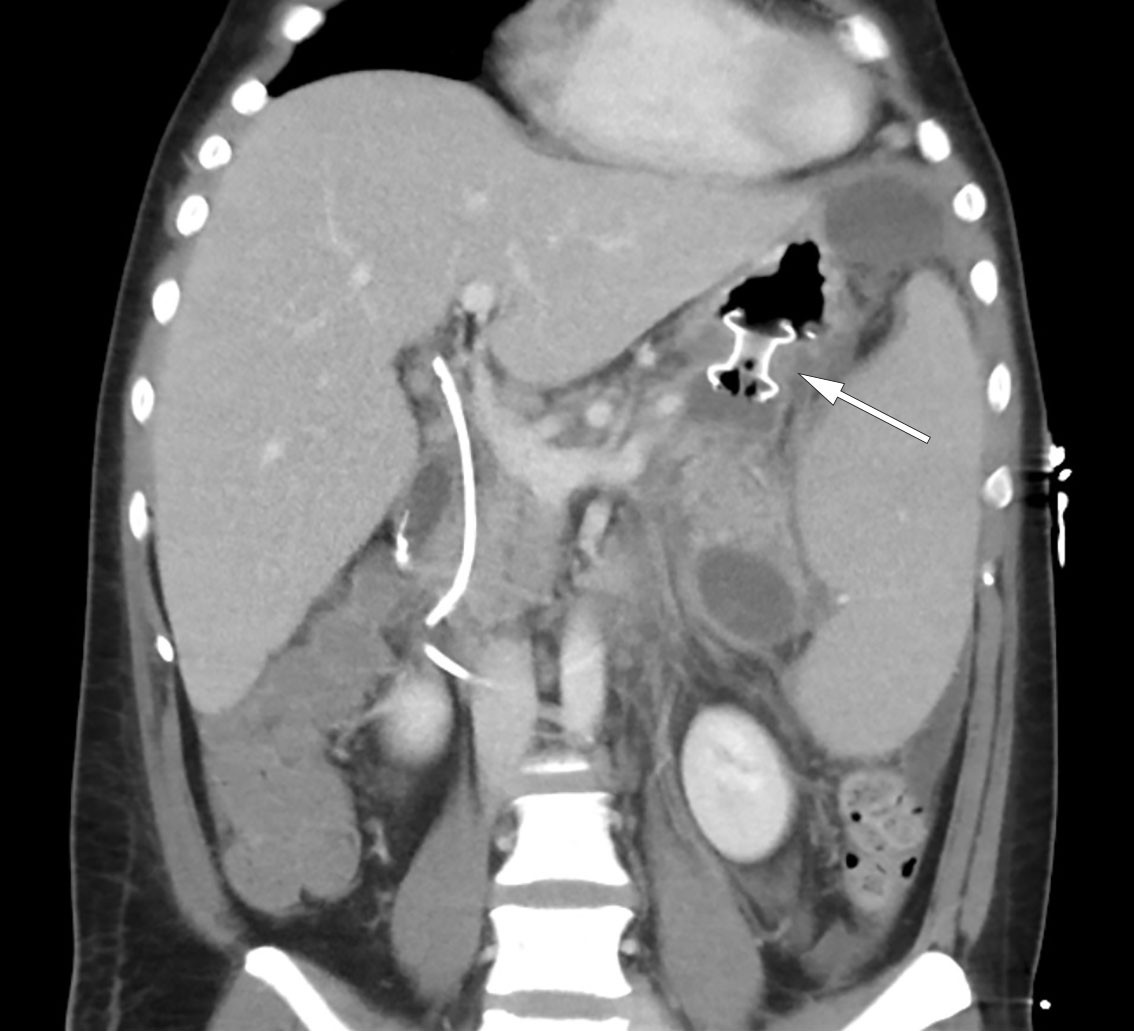

MRCP-undersøkelse samme dag viste peripankreatiske væskeansamlinger og et 4 mm stort konkrement distalt i ductus choledochus (figur 1). I tillegg forelå uttalte pankreatittforandringer med omkringliggende ødem og væskeansamlinger i øvre abdomen. Tredje dag etter innleggelsen var pasienten ytterligere medtatt og smertepåvirket samt plaget av kvalme. Blodprøver viste vedvarende leukocytose på 45,6 × 109/L. CRP-nivået hadde økt til 261 mg/L, og bilirubinnivået hadde steget videre til 290 µmol/L. Det ble startet bredspektret, intravenøs antibiotikabehandling i form av piperacillin/tazobaktam 4 g/0,5 g tre ganger daglig på mistanke om samtidig infeksjon i galleveier. Videre ble pasienten henvist til endoskopisk retrograd kolangiografi (ERC), som ble utført ukomplisert med papillotomi fulgt av fjerning av to sorte konkrementer i distale choledochus. Galleblæren var pakket med konkrementer ved kolangiografi. Det ble i etterkant samme dag målt bilirubinnivå fallende til 139 µmol/L.

Den kliniske tilstanden ble i løpet av tredje døgn ytterligere forverret med sterke magesmerter. Pasienten ble overflyttet til intensivavdeling grunnet begynnende organsvikt med O2-behov. Pasienten var somnolent, men selvpustende, og i behov av 2–3 L O2 på nesekateter for å opprettholde adekvat oksygenmetning > 92 %. Videre forelå stigende INR-verdi på 1,9 samt fallende albuminverdi på 22 g/L (fra 45,6 g/L), som ga mistanke om blødningsforstyrrelse. I tillegg tilkom ny stigning i bilirubinnivå til 290 µmol/L, men i fravær av øvrig stigende nivå av lever- og galleprøver ble behov for ny ERC-undersøkelse avventet etter tverrfaglig diskusjon. Ytterligere diagnostikk med CT av abdomen og bekken viste nekrotiserende pankreatitt med peripankreatiske væskeansamlinger samt fri væske i buken (figur 2). Det var ingen tegn til intra- eller ekstrahepatisk kolestase. Videre forelå bilateral pleuravæske og sammenfalt lungevev, som kunne forklare pasientens respiratoriske forverring. I lys av forhøyet INR-verdi ble det avstått fra pleuratapping. I tillegg ble det bemerket forstørret milt (største lengde 21 cm).